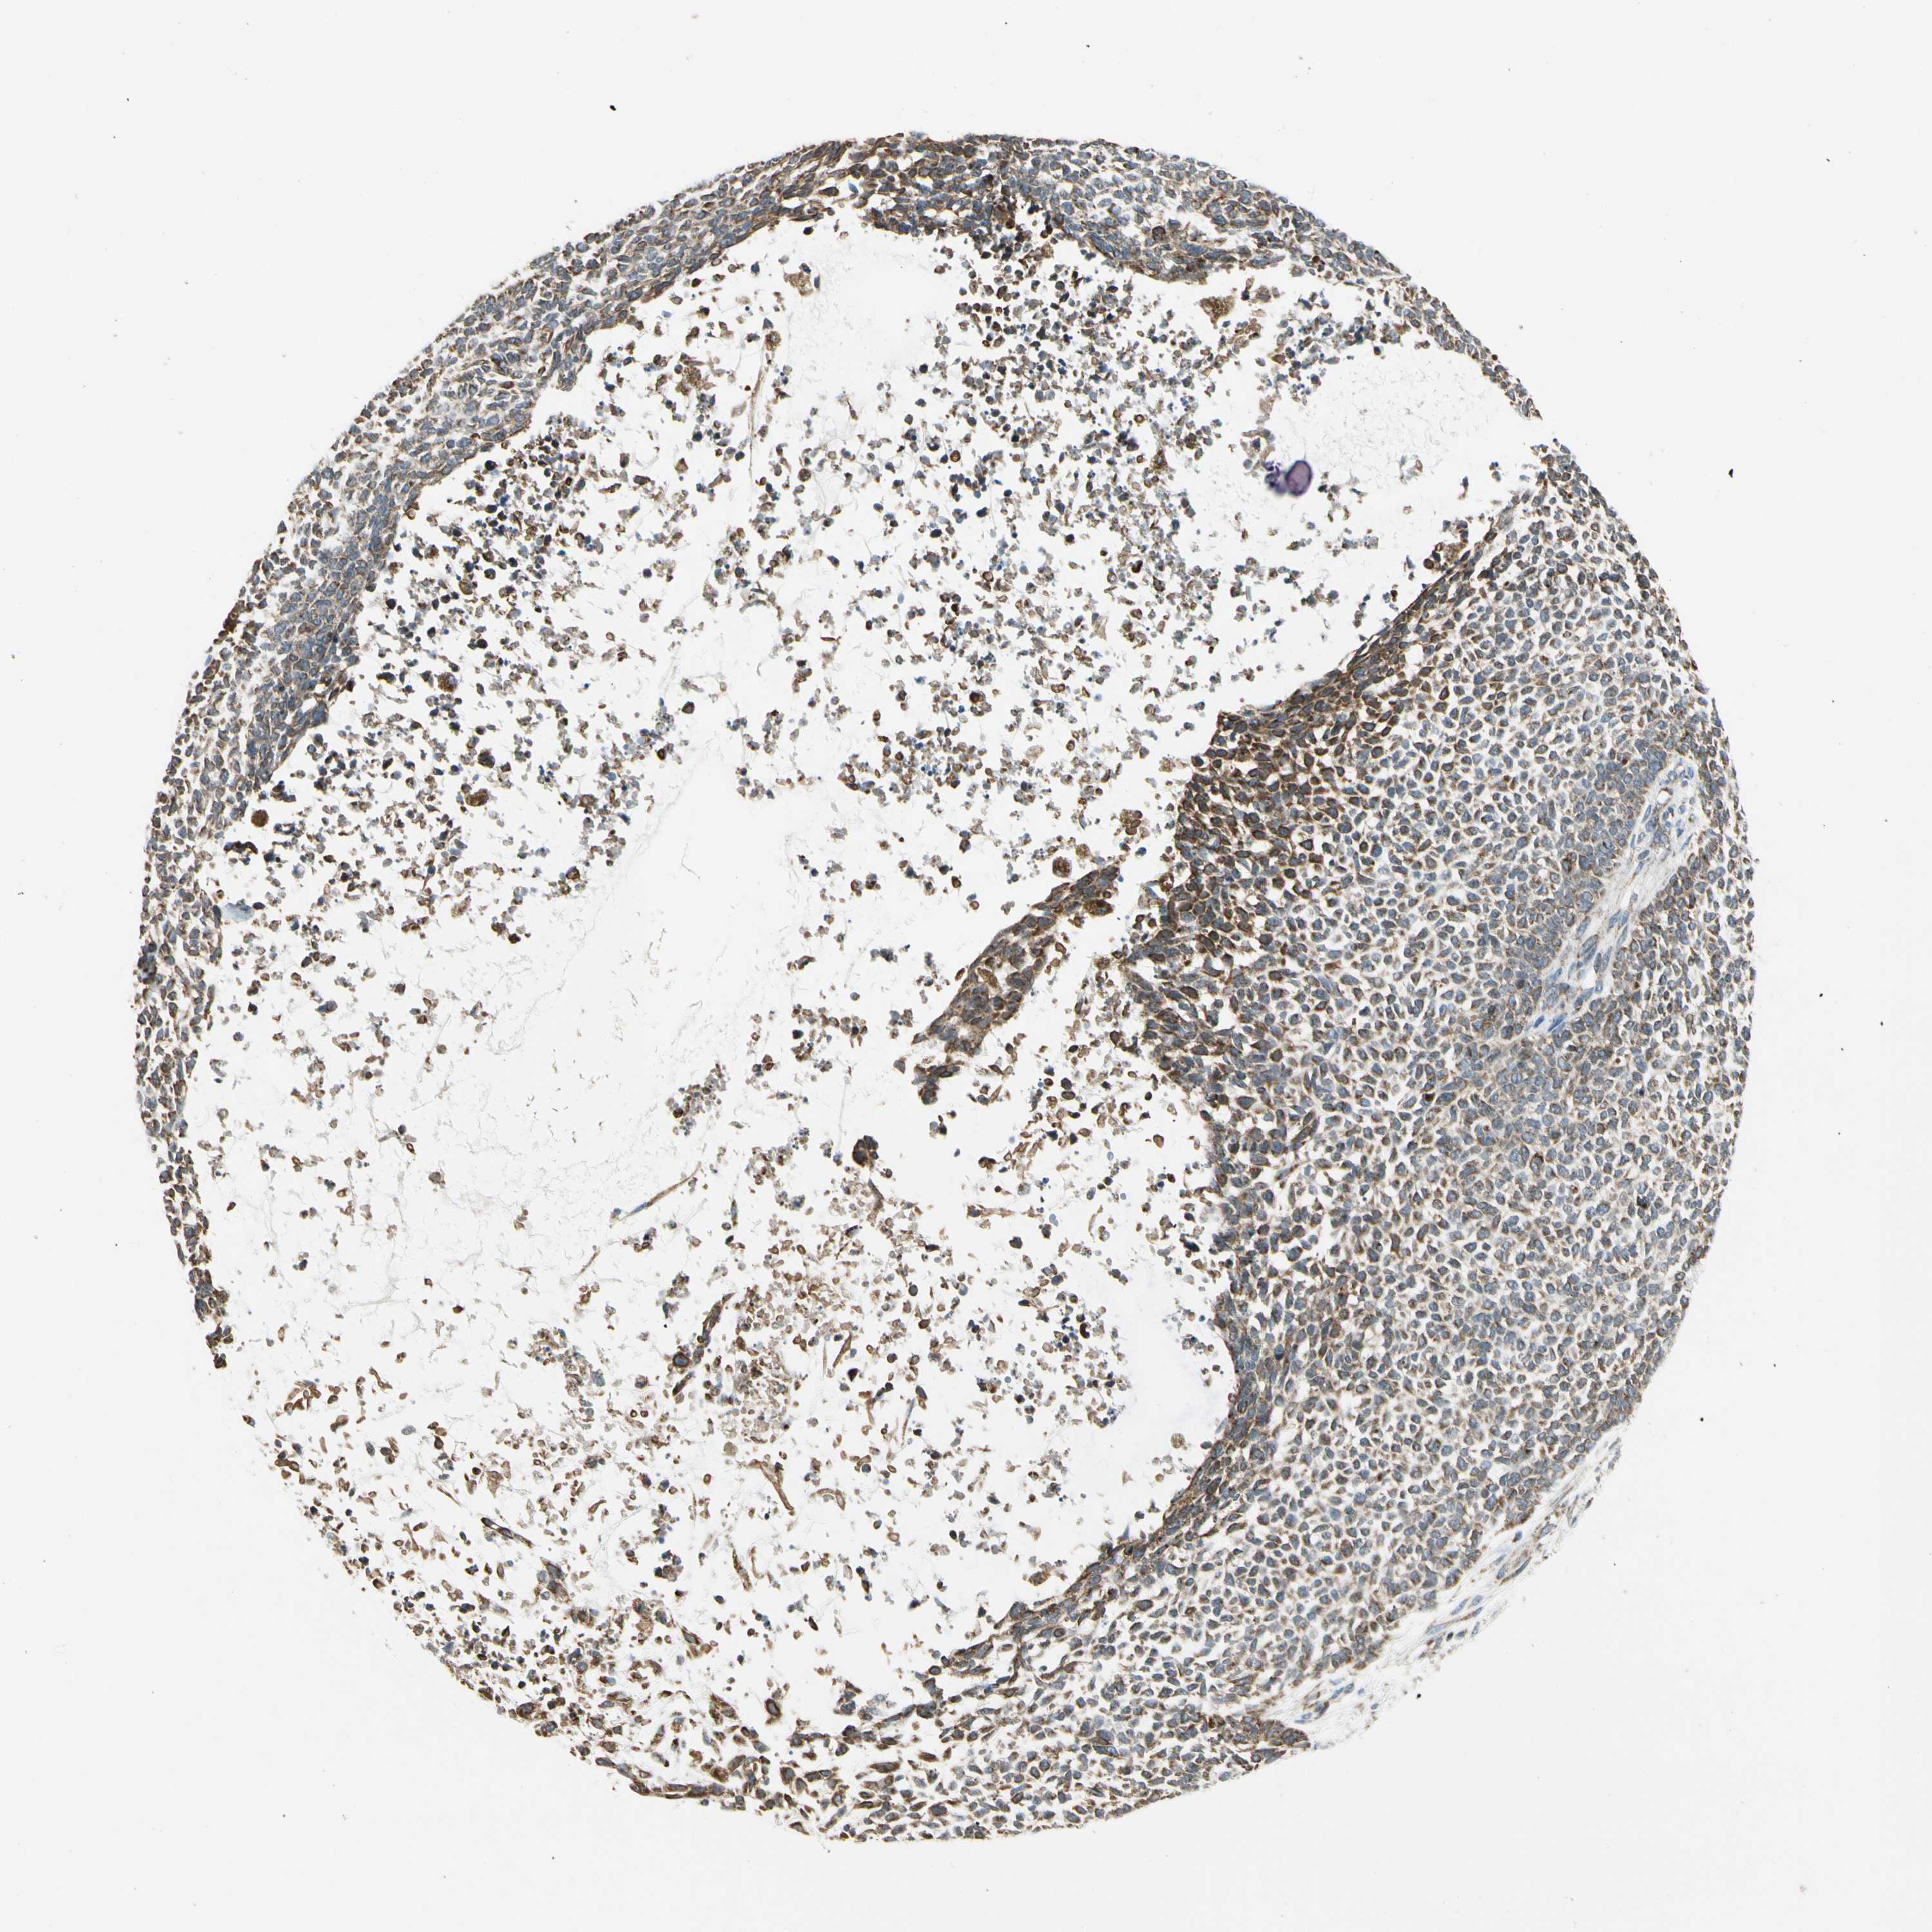

CANCER SKIN CANCER Show tissue menu

SKIN CANCER - Protein expressioni

A mouse-over function shows sample information and annotation data. Click on an image to view it in a full screen mode. Samples can be filtered based on level of antibody staining by selecting one or several of the following categories: high, medium, low and not detected. The assay and annotation is described here.

Each image is clickable and will lead to virtual microscopy that enables deeper exploration of all samples and also displays staining intensity scores, fraction scores and subcellular localization as well as patient and tissue information for each sample.

Antibody HPA007698

Antibody HPA008184

Antibody CAB034350

Staining

High

Medium

Low

Not detected

Intensity

Strong

Moderate

Weak

Negative

Quantity

>75%

75%-25%

<25%

None

Location

Nuclear

Cytoplasmic/membranous

Cytoplasmic/membranous,nuclear

Squamous cell carcinoma, NOS

Basal cell carcinoma

BCC, high aggressive